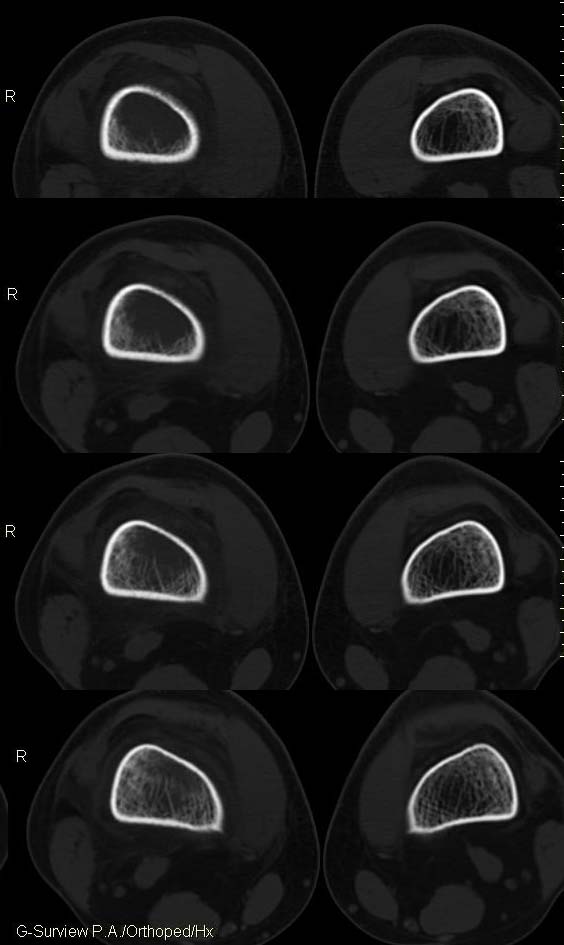

20岁,男,右股骨下端疼痛一个月,无发热,白细胞正常,皮肤不红,肿胀,触痛。

右股骨下端很长范围内的髓腔扩大,骨小梁破坏消失,皮质亦呈融骨性破坏,周围脂肪层次紊乱,肌肉受累及密度减低。考虑为:恶性骨肿瘤。请专家们分析骨肉瘤及尤文氏肉瘤的ct征象。

6.ct及mri:能较好地判断肿瘤的范围及侵犯软组织的情况。mri可见瘤体处广泛性骨质破坏,呈软组织肿块影;在t1加权像上呈均匀的长t1信号;在t2加权像上呈很长t2高信号。在ct上显示为源于骨组织的软组织肿块,骨质广泛破坏。

长骨ct见的较少,该病例股骨下端表现为边缘模糊的溶骨性破坏,伴有费用性脱钙,髓腔密度增高,呈毛玻璃样改变,病变周围软组织肿胀,脂肪间隙模糊,无骨膜反应,应密切结合临床,考虑骨纤维肉瘤或慢性骨脓肿。期待结果。

此病例基本可定是恶性骨肿瘤:髓腔内长范围肿块、皮质不规则破坏、软块及软组织浸润、瘤骨及不规则骨膜反应等。可以肯定地除外炎性病变和骨纤。

结合临床还是将尤文氏肉瘤放在前面,骨肉瘤不排除。纤维肉瘤及恶纤组多见老年人,不放在首要诊断范围内。